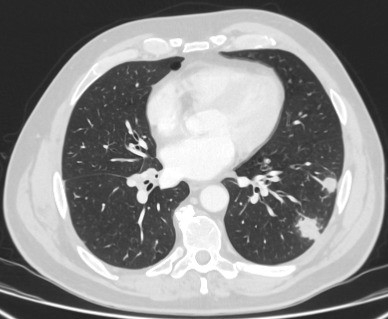

Tomografia computadorizada (TC) mostrando um pequeno nódulo no lobo superior esquerdo com margens lisas, posteriormente considerado uma metástase colorretal solitária na ressecção

Do acervo de Dr. George Tsaknis, MD, PhD, FRCP (Londres), MRQA, MAcadMEd, PGCert; usado com permissão